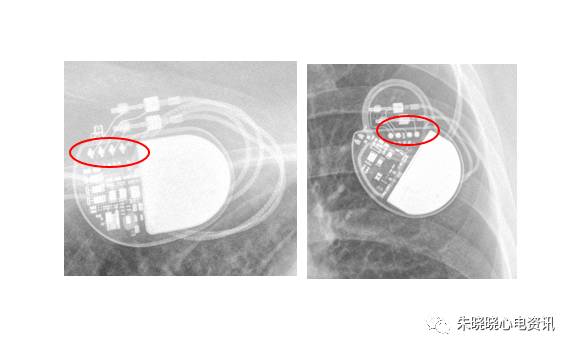

波士顿科学起搏器部分接线为数条导线并排,可联想为蜈蚣帮助记忆(图9)

图9 波士顿科学起搏器

另有部分起搏器接线方式像长梯(图10)

图10 波士顿科学起搏器

百多力起搏器接线部分和餐桌上的碗筷组合相似(图11)

图11 百多力起搏器

索林的起搏器接线方式像短梯(图12)

图12 索林起搏器